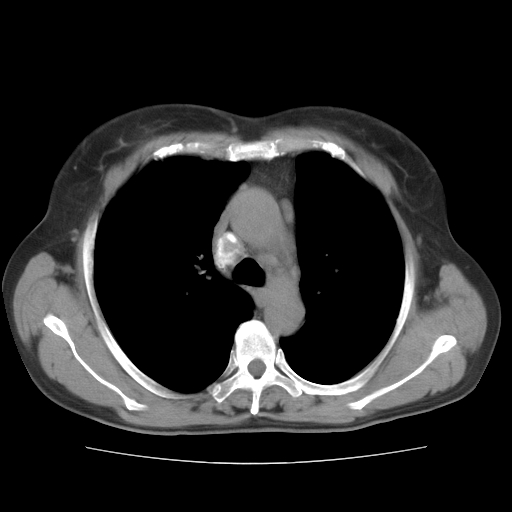

标题: CT10838:女性,56岁,是上腔静脉钙化还是淋巴结钙化? [打印本页]

标题: CT10838:女性,56岁,是上腔静脉钙化还是淋巴结钙化?

女性,56岁临床诊断为胃贲门ca,术前检查发现,此钙化灶,对此科内稍有争论!请各位老师看看!是上腔的还是淋巴结的?有意义吗?

淋巴结钙化,上腔静脉在外侧可看到.

支持淋巴结钙化,气管前胸骨后也有.

胸锁关节层面的是淋巴结钙化,气管前腔静脉后的钙化灶占了4个层面,不知层厚是多少?看样子应该是7--10毫米之间,那么这病灶最小纵径得有28毫米!应该提示点什么了,没传肺窗,估计肺内没有病变?

左锁骨下静脉和头臂静脉会合后形成是上腔静脉,此钙化位于两血管回合的腔静脉后方、气管右前方,这个位置没有其他结构,应该是淋巴结钙化。一般多为淋巴结核后钙化,没有临床意义。